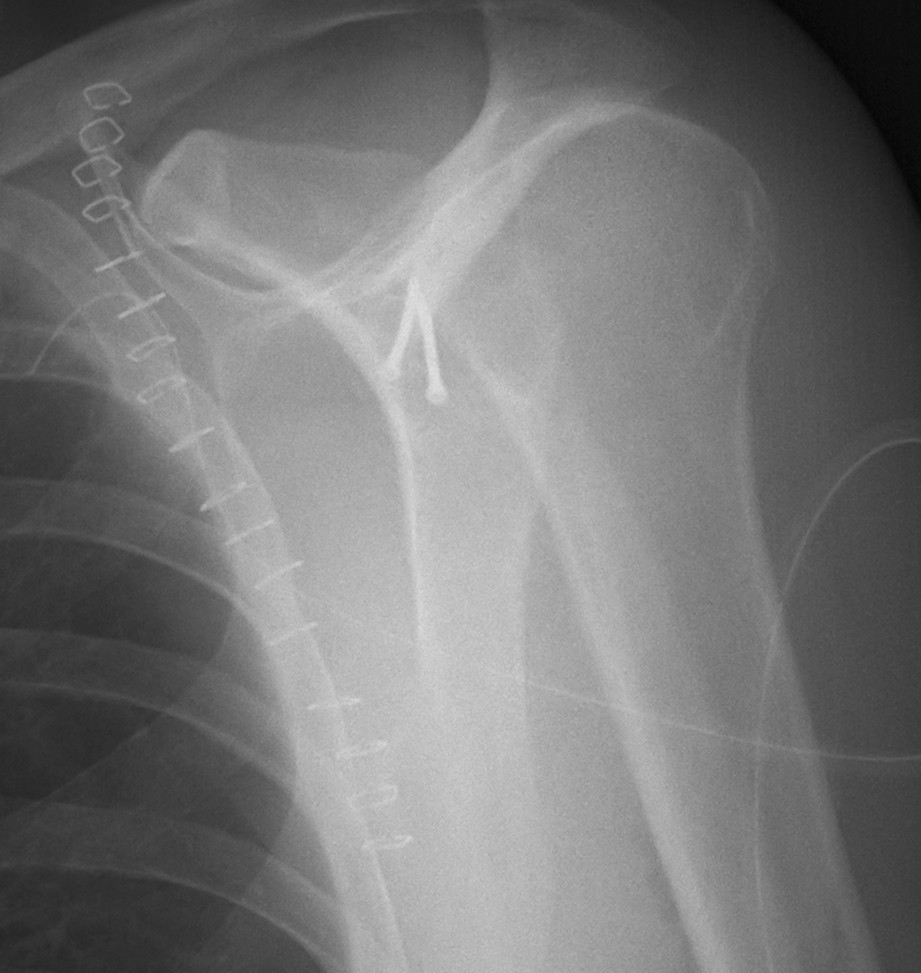

B. Neck

Indications for surgery

- > 450 angulation

- > 10 mm displaced (i.e. medial displacement

Case 1

- > 1 cm medial displacement

- ORIF via posterior / modified Judet approach

Case 2